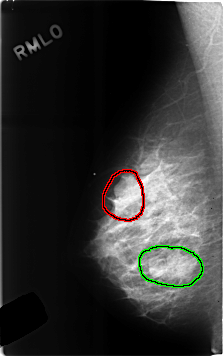

C_0306_1.RIGHT_MLO

RIGHT_MLO LINES 4624 PIXELS_PER_LINE 2904 BITS_PER_PIXEL 12 RESOLUTION 50 OVERLAY

FILE: C_0306_1.RIGHT_MLO.OVERLAY

TOTAL_ABNORMALITIES 2

ABNORMALITY 1

LESION_TYPE MASS SHAPE LOBULATED MARGINS OBSCURED

ASSESSMENT 4

SUBTLETY 5

PATHOLOGY BENIGN

ABNORMALITY 2